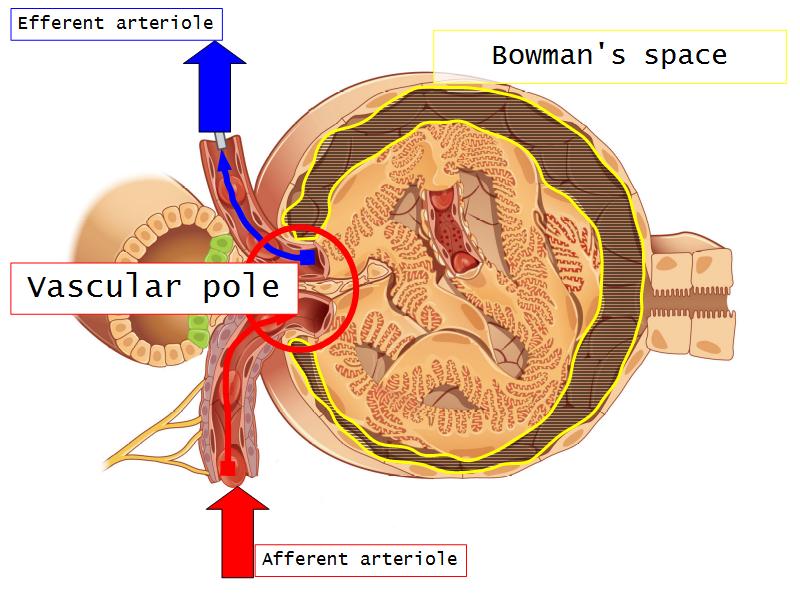

- The renal corpuscle

- Make an annotated diagram of a nephron, including the juxtaglomerular apparatus. Indicate the flow of blood and water in each part, and how solutes are filtered, secreted and reabsorbed.